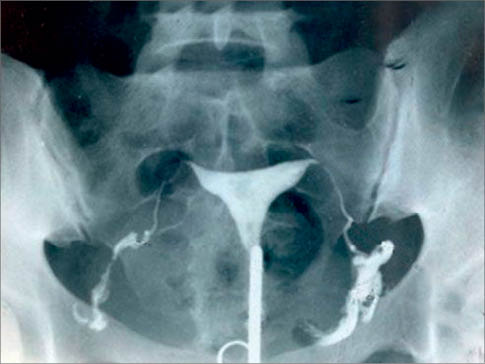

Планирование второй и последующей БПланирую 2 Б, пью витамины, муж худеет, спорт, пп, мечтаем о сыне... Все как у всех можно сказать, сдала анализы, все прекрасно, нашла кс где 2 буду делать (там где рожала первый раз врагу не пожелаешь), решила съездить в платную сдать на вирусы, чтобы точно ни чем внутриутробно не заразить ребенка (ЦМВ инфекция внутриутробная у дочки была) Нашла врача хорошего, она все посмотрела и предложила сходить на узи, для своего успокоения, потому, что прошло 2,4 года, шов от кс точно зажил, сейчас такие нитки, такие иголки все д.б. хорошо. Но я все таки пошла и тут БАЦ......... ПРОСТО ШОК.................................... Шов от кс расходится, нишу нашли, загремела в больницу, положили, хотели делать гистероскопию, хорошо, что перед ней сделали другую операцию, на которой сделали рентген и обнаружили, что цервикальный канал и шейка матки не пропустит аппарат гидроскоп, т.к. там все нахрен зашито и срослось... чудом каким-то осталось не большое отверстие, через которое выходит кровь и овуля.... короче квоту на операцию в Москву оформляем.....чтобы делать метропластику........ Больше цинзурных слов у меня простите нет.........................................................